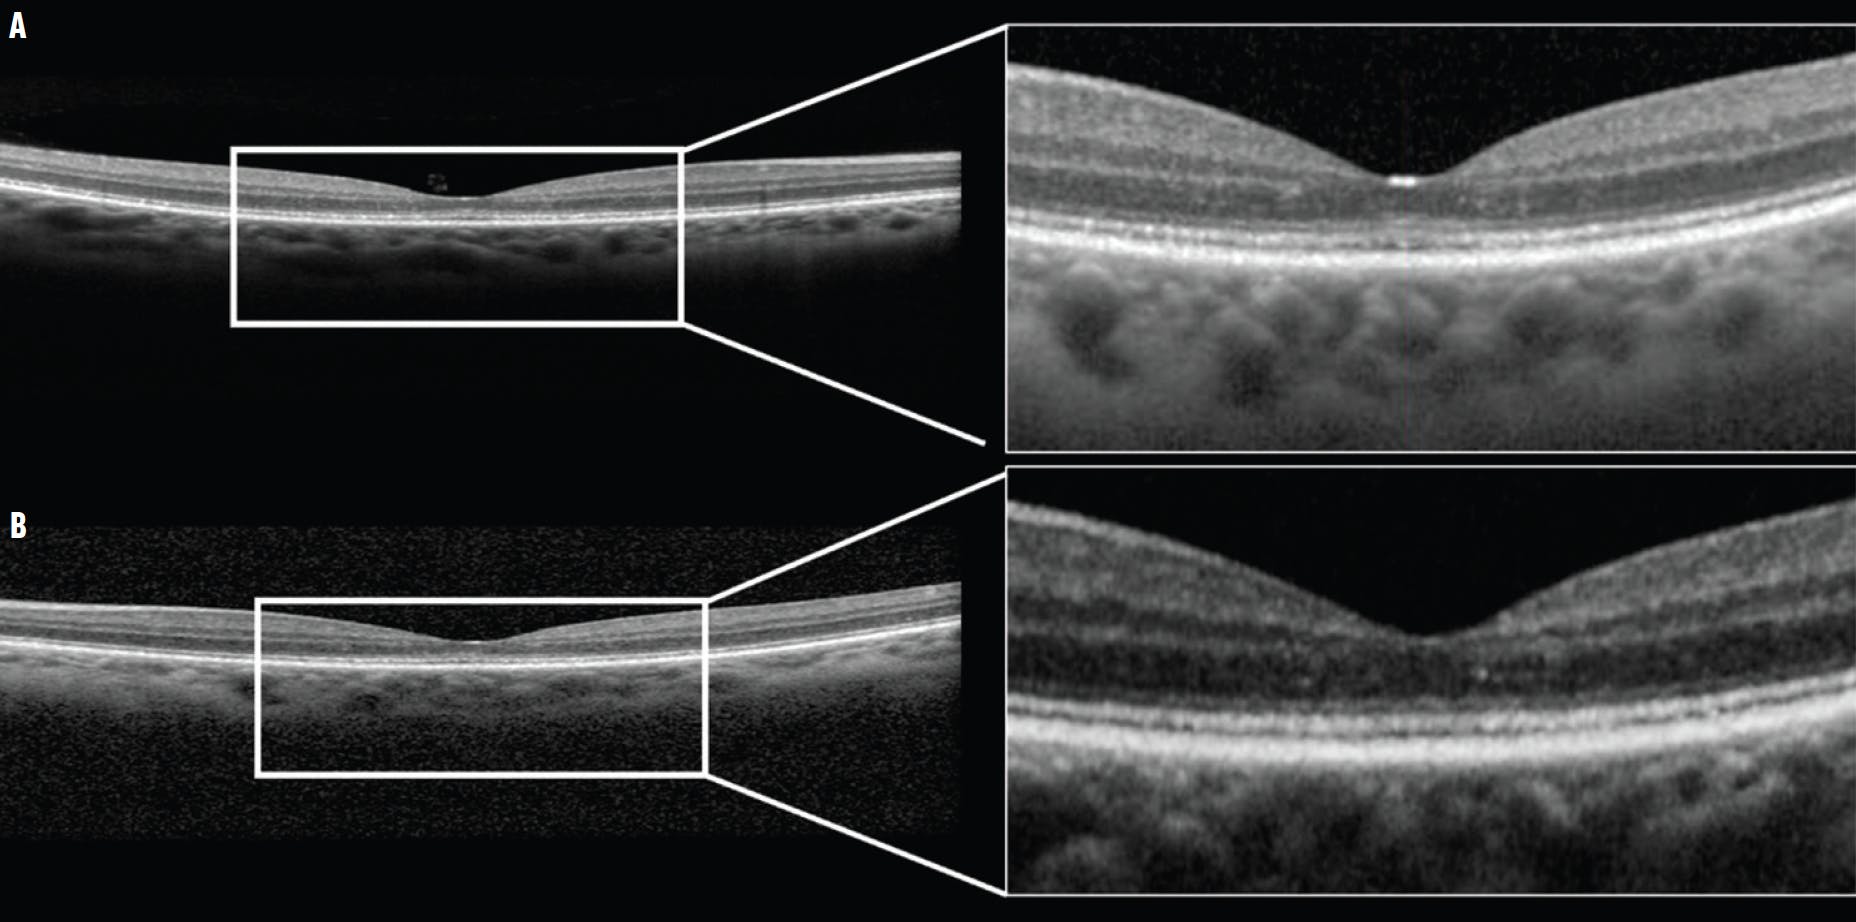

Fundus autofluorescence, microperimetry, and OCT imaging were unremarkable. A more detailed examination revealed an indistinct ellipsoid zone (EZ; Figure 1). A full-field electroretinogram (ERG) was performed, and its findings were compatible with moderate, generalized cone dysfunction in each eye. A multifocal ERG showed bilateral foveal suppression (Figure 2).

<p>Figure 1. The OCT scans of the right (A) and left (B) eye show a disrupted EZ.</p>

Figure 1. The OCT scans of the right (A) and left (B) eye show a disrupted EZ.

Patients often present with a gradual decrease in visual acuity, frequent photophobia, and light sensitivity.6-8 Classic OMD is characterized by a blurred EZ and the absence of the interdigitation zone on OCT. Based on the severity of interdigitation zone and EZ involvement, the clinical presentation of OMD can be categorized into three stages, which appear to be related to the duration of disease onset.6,9,10 In late stages, studies have reported thinning of the outer nuclear layer with preservation of the RPE.11-13 Full-field ERG may show a reduced cone response (although variable), and multifocal ERG often shows a reduced response in the foveal area, playing a key role in OMD diagnosis.6